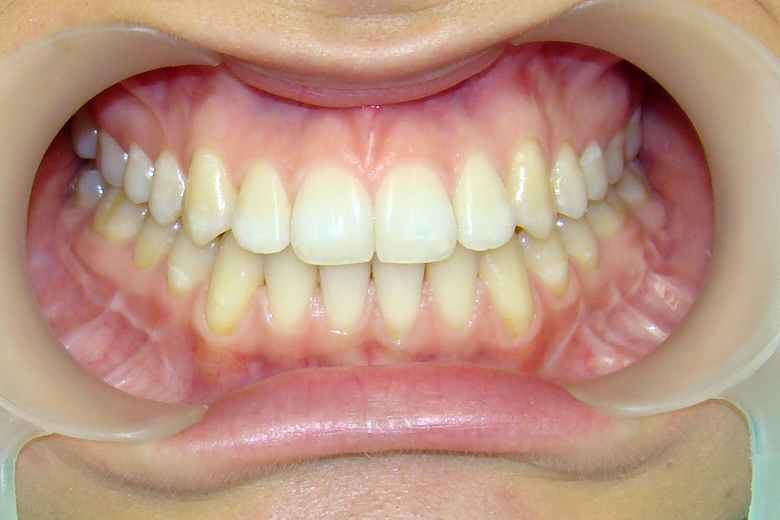

Девушке 14 лет. Получилось все исправить без удаления зубов

А это уже молодой человек 10 лет. Тоже получилось справиться без удаления. Хоть оно и было показано. Но мальчик очень упорно носил специальные аппаратики и резиночки. Покажу со всех сторон. Этот случай победил в конкурсе на конференции